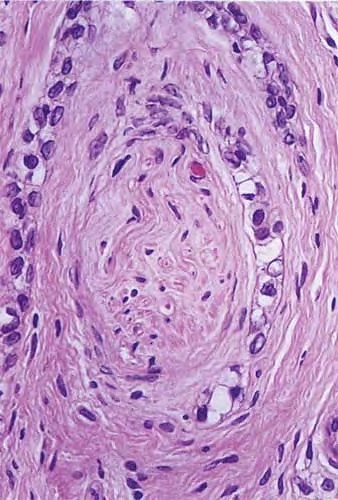

microcystic-adnexal-carcinoma